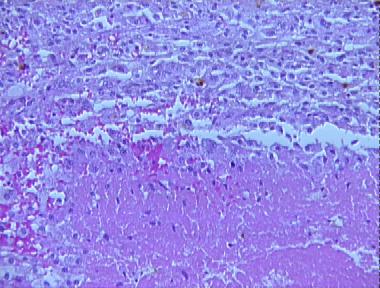

epitheliod sarcoma

Histologic Features